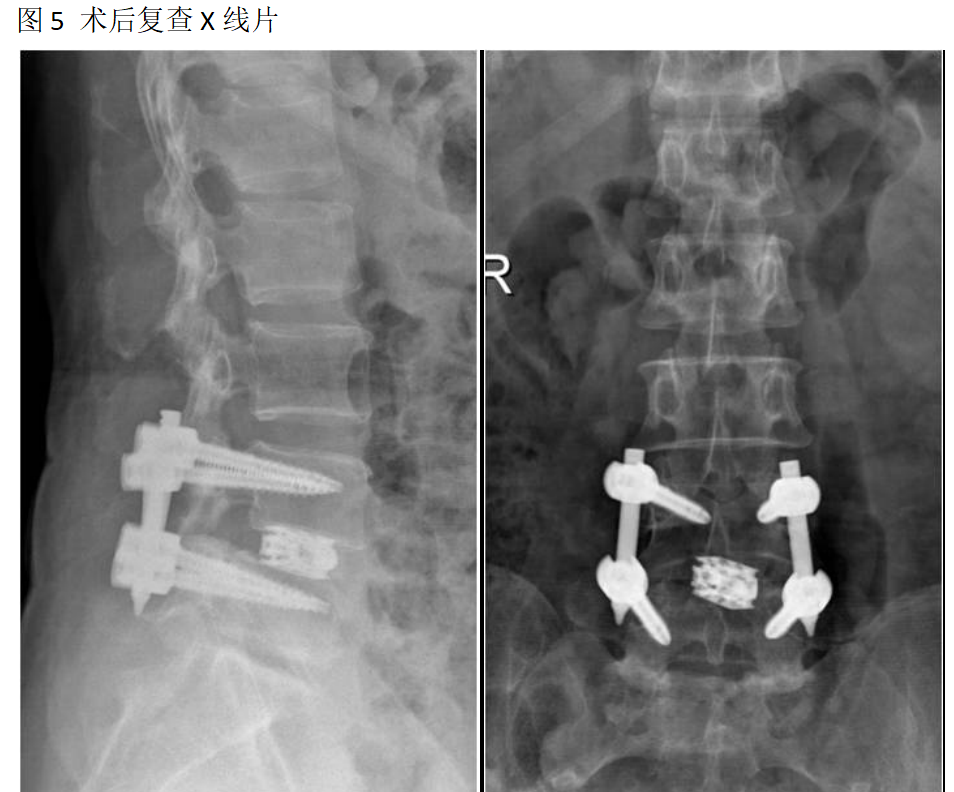

吕X,女,56岁。

主诉:腰疼及双下肢疼痛麻木伴活动受限3年加重半年。

查体:L4-5棘间及椎旁压痛,右下肢直腿抬高试验60°阳性,左下肢50°阳性,双下肢肌力肌张力正常。